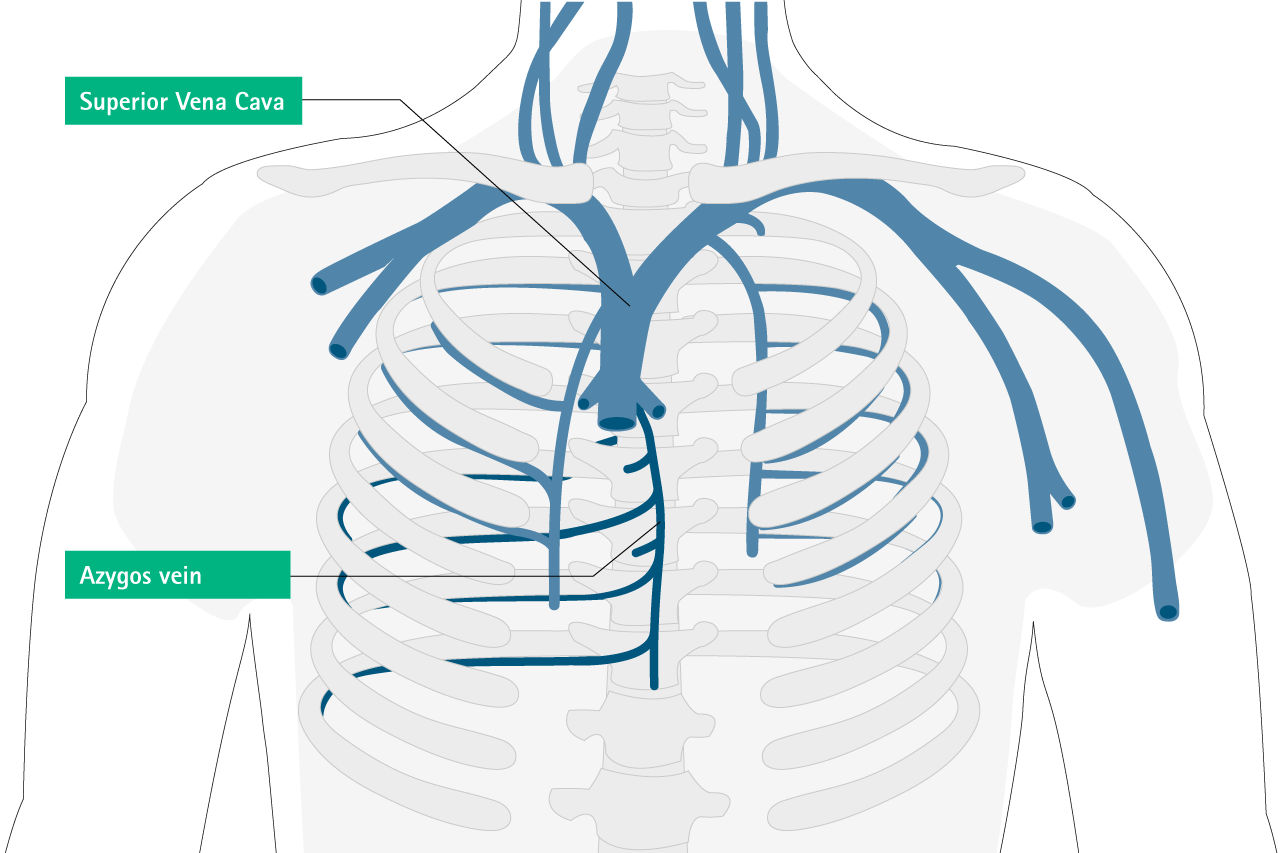

Type and Position of Catheter Misplacement 12

Intravascular Misplacement

Extravascular Misplacement

Carotid arteryExtradural space

Azygos veinPericardium

Paersistent left sided superior vena cavaPleural space

Internal thoracic (mammarx) veinMediastinum

Vertebral veinThoracic duct